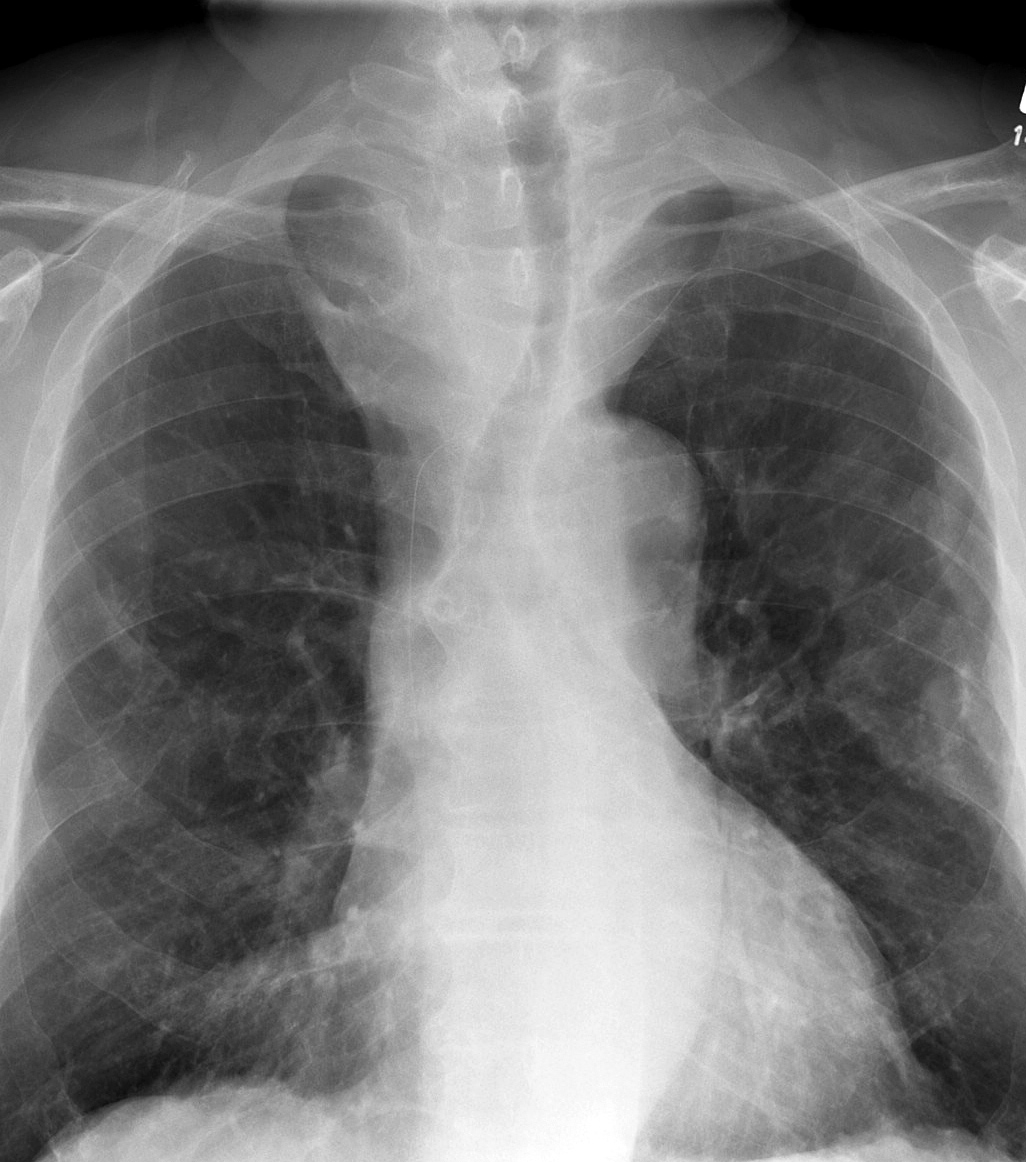

Thyroid Mass

Case 11 PA